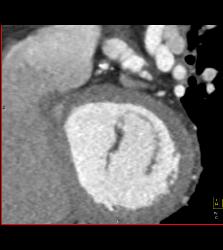

CCTA: Left Anterior Descending Coronary Artery (LAD) Plaque Without Critical Stenosis